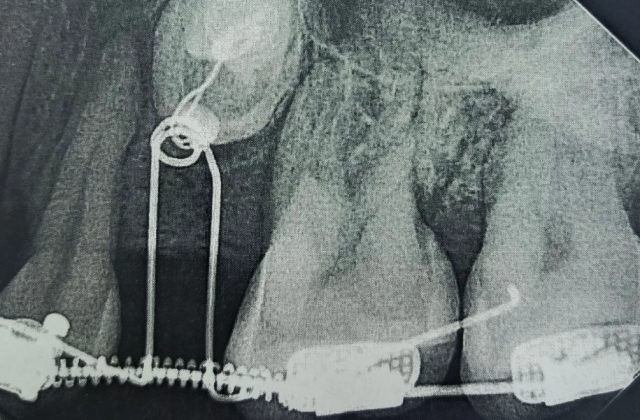

Женщина обратилась в областную стоматологическую поликлинику ещё в 2023 году. Врачи провели тщательное обследование с компьютерной томографией: оно позволило детально оценить положение непрорезавшихся зубов относительно других элементов зубочелюстной системы. У женщины в ряду не было одного зуба, а другой был намного меньше нормы. Из-за этого врачи решили «переместить» их в ряд. Пациентке установили брекеты и 1,5 года создавали место для этих зубов. После хирургического раскрытия коронок ретенированных зубов стоматологи зафиксировали ортодонтические кнопки для вытяжения. С помощью дополнительных рычагов и пружин один из зубов уже вышел из костной ткани, а второй проходит кортикальную пластинку, то есть – прорезается.